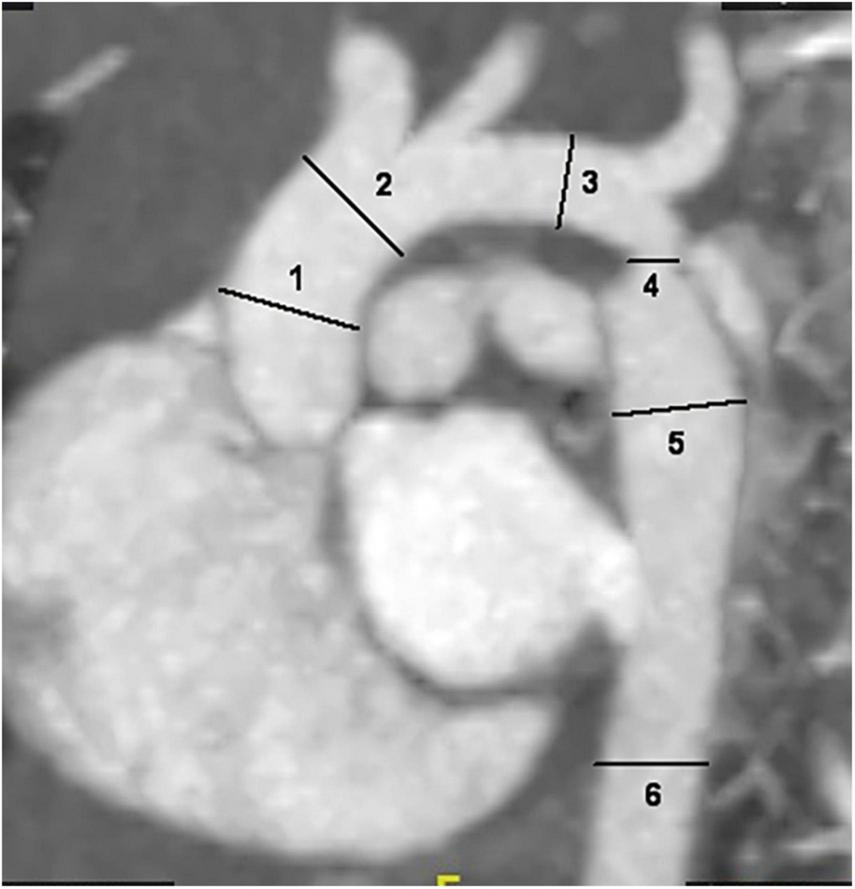

The internal diameter of the aorta at all levels and concomitant cardiac malformations, including bivalvular aortic valve (BAV), aortic arch hypoplasia, PDA, VSD and ASD, were recorded. Two radiologists performed image measurements at the same time, and the average of both measurements was calculated to reduce the error of the data. The intracardiac malformations and cardiac valves were evaluated by transthoracic echocardiography. The diameter of the aorta was measured at the following six locations: ascending aorta at its maximum diameter (ascending aorta); aorta proximal to the origin of the brachiocephalic trunk (pre-coarctation aorta); aortic arch at the largest size (aortic arch); coarctation site at the narrowest size (coarctation site); widest region of the descending aorta (post-coarctation aorta); and descending aorta at the level of the diaphragm (Figure 1; 19–21). The aorta measurement was performed along the vertical direction of the long axis of the aorta in the median sagittal plane of the aortic arch. The ratio of the aortic diameter at the coarctation site to that at the diaphragm (coarctation site-diaphragm ratio, CDR) was calculated to describe the degree of coarctation as follows: CDR < 75%, diagnosed as aortic coarctation; 50% < CDR > 75%, diagnosed as mild coarctation; and CDR < 50%, diagnosed as severe coarctation (22, 23). To account for growth-related changes, the aortic diameter was normalized to a Z score, which was the ratio of aortic diameter to the square root of body surface area. If the Z score was more than 2, aortic dilatation was considered (24, 25). The body surface area (BSA) was calculated by the DuBois formula (26) and aortic dilatation was defined as a main artery Z score > 2.0 (24).

Sagittal multiplanar reformatted image shows the measurement of aortic diameters at different levels: 1. ascending aorta; 2. pre-coarctation aorta; 3. aortic arch; 4. site of coarctation; 5. descending aorta after the site of coarctation; 6. descending aorta at level of diaphragm.